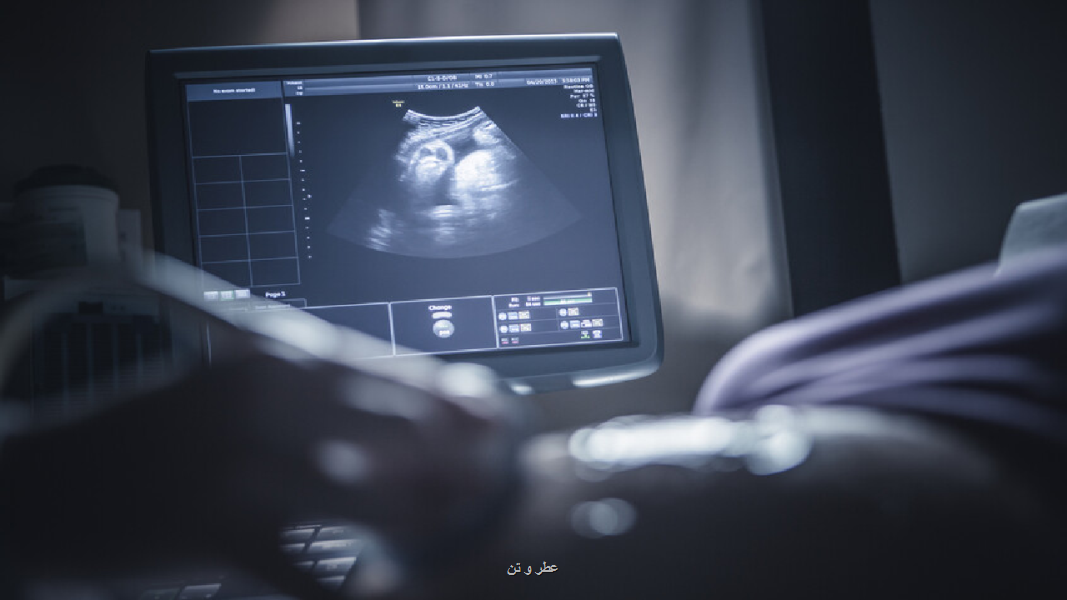

این مطالعه گروهی از زنان آبستن را در سه بیمارستان بزرگ بارسلونا دنبال کرد. 132 نوزاد در ماه اول تحت اسکن MRI پیشرفته قرار گرفتند تا بلوغ مغز آنها با اندازه گیری پیشرفت میلین سازی ارزیابی شود.